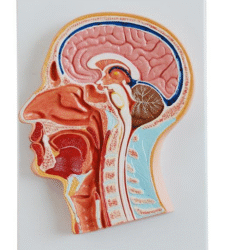

ATL-11 MALE MUSCLES FIGURE INTERNAL ORGANS HARD

The model is an anatomically accurate representation of the human anatomy, complete with superficial and deep musculature, the digestive system, lymphatic system, respiratory system, urinary system, circulatory system, endocrine system, and nervous system. Our model has removable organs and dissectible features for a complete educational experience.